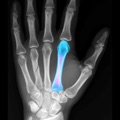

BoneGauge allows you to approximate an individual's bone density and quality from a mobile platform. BoneGauge helps you make measurements of cortical thickness of the second metacarpal from either hand or wrist x-rays. Use your smart phone camera to take a photo of the second metacarpal on an x-ray, or make measurements from an image saved in your photo library.

BoneGauge accurately calculates 2nd metacarpal cortical percentage (2MCP) in a semi-automated fashion. 2MCP has been shown to correlate with hip bone mineral density and T scores from DXA scans. Measurements made in the app will be uploaded to a central database. When combined with a patient's age, gender, and DXA score, past measurements will also help the improve the accuracy of future measurements.

This app allows you to estimate an individual's global T score in an office or hospital setting, by simply taking a photo of the 2nd metacarpal. While this measurement may not completely replace DXA, it may help a clinician screen a patient's bone quality to assist in treatment decisions and determine who may benefit from further bone density testing or osteoporosis treatment.

• Screenshot #4 pour BoneGauge